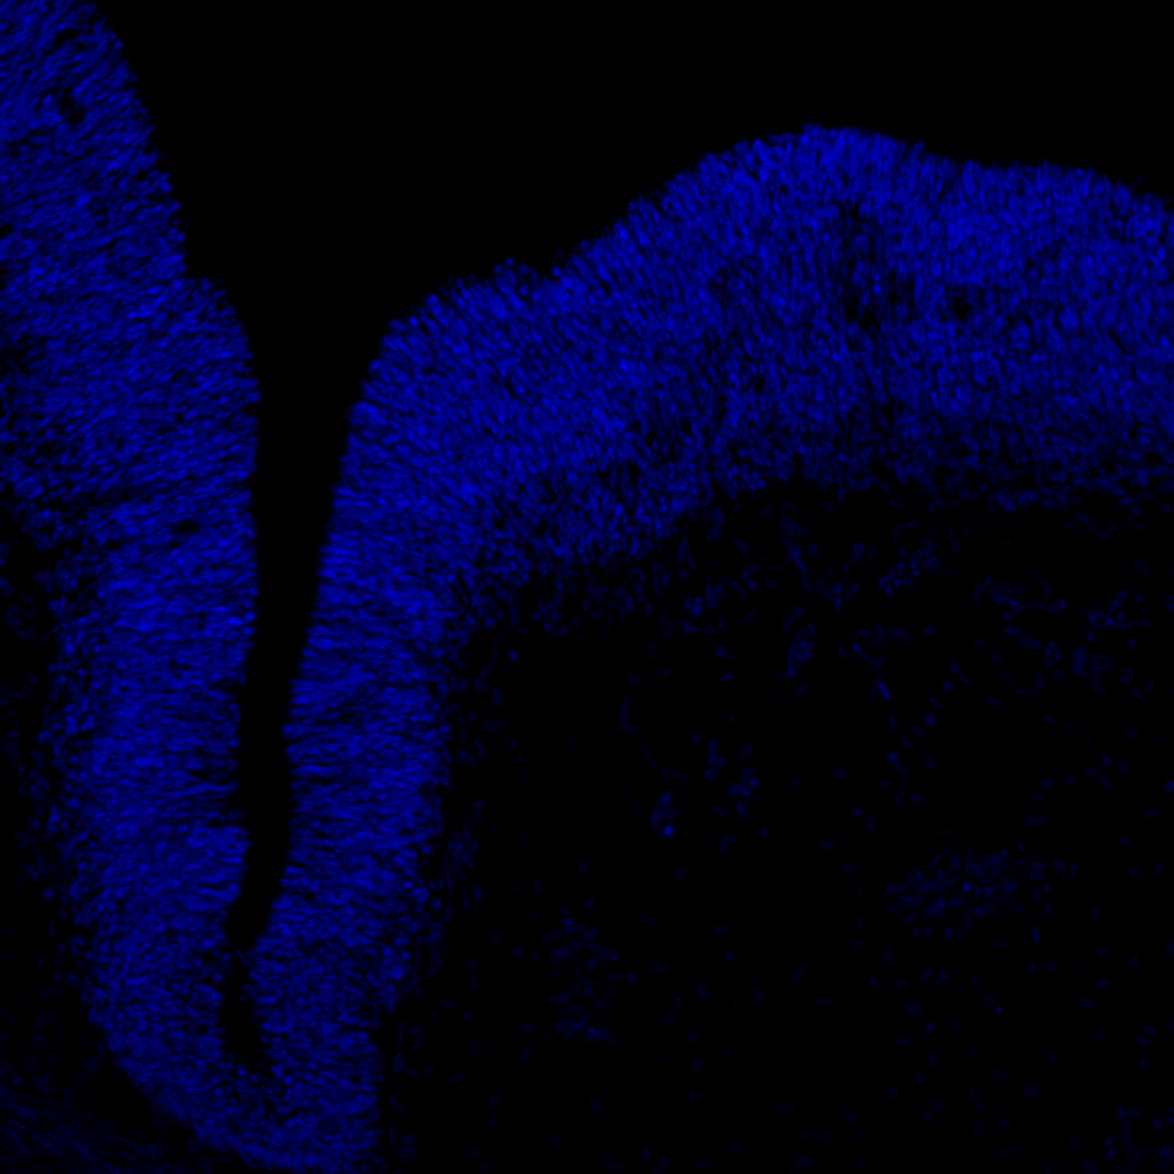

DAPI

6PCW human midbrain